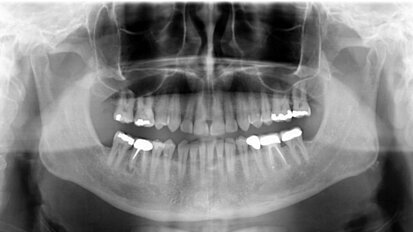

Minimalnie inwazyjne rozwiązania implantoprotetyczne w zaniku poziomym kości szczęki i żuchwy

Autorzy przedstawiają przypadki pacjentów z bardzo zaawansowanym poziomym zanikiem kości szczęki i żuchwy. Na podstawie szczegółowej ...